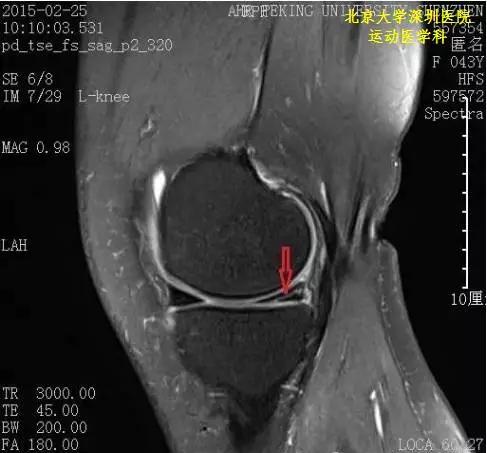

骨科基础丨半月板损伤磁共振表现

半月板损伤磁共振图解

半月板核磁共振图解析

半月板磁共振图解

半月板3度撕裂共振图